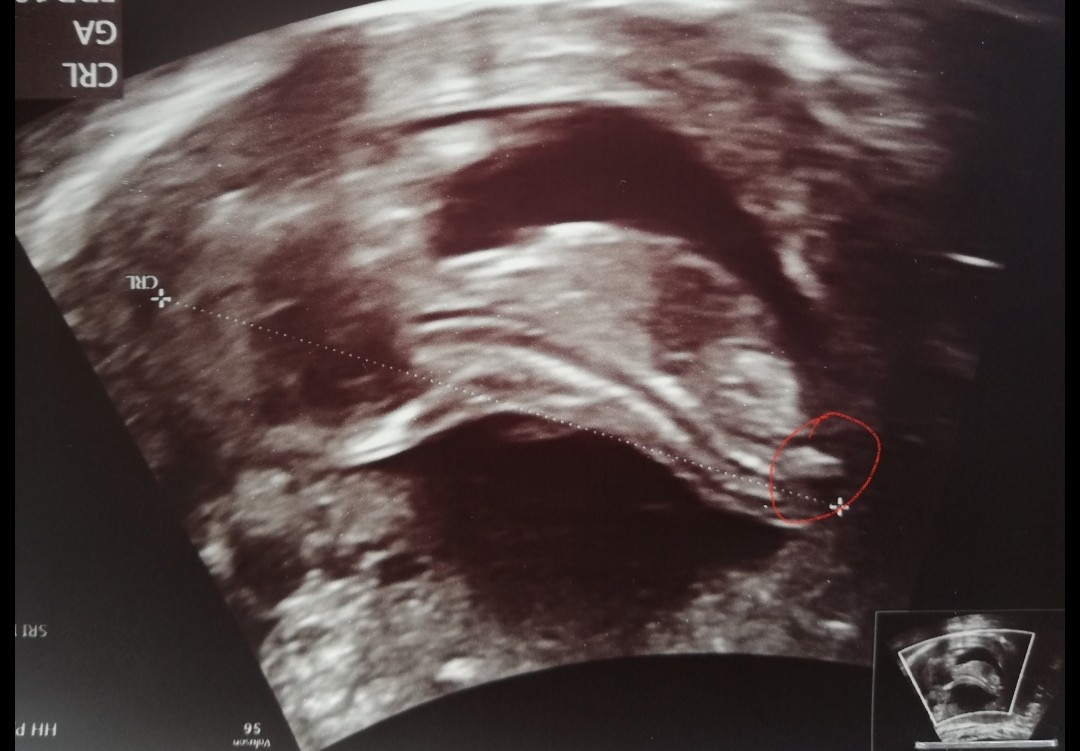

A na tym zdjęciu co dziś wstawiłam nie widzisz widełek? Na tym wczorajszym na grupie ramzi i nub, dziewczyny napisały że nie widać wyrostka. A na tym myślę, że coś widać 😁

Zobacz tam na tym końcu? Czy mi już znowu się coś wydaje 😂

Załączniki

• IMG_20200604_213917.jpg

IMG_20200604_213917.jpg

396,1 KB · Wyświetleń: 82

Ja wiem o które miejsce wczoraj Ci chodziło, bo sama tak myślalam. Ale to było za nisko, tak jakby przedłużenie kręgosłupa 😅 tutaj też mam wrażenie, że w sumie to może nie być nub bo też trochę nisko. Wyżej niż to wczoraj, ale nisko

Dziewczyny u nas wszystko okej [emoji176] wszystkiej parametry dobre, serduszko bije 163/min. Dzidzia ma 6,72cm, ryzyko wad niskie. No i jestem szczęśliwa, bo najprawdopodobniej będzie córcia [emoji7] ewidentnie było widać widełki [emoji179]